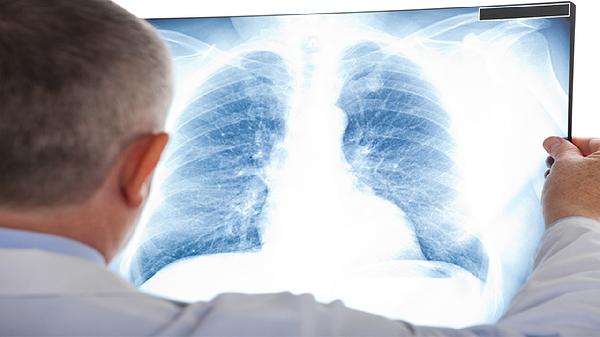

肺部结节可分为单发和多发两种类型,主要通过影像学检查判断数量差异,单发指孤立性结节,多发指同时存在两个及以上结节。

单发结节通常表现为肺组织内单个圆形或类圆形病灶,直径多在30毫米以内,边界可能清晰或模糊。这类结节常见于结核球、错构瘤或早期肺癌,需结合结节形态、生长速度及患者吸烟史综合评估。CT检查可显示钙化、毛刺征等特征,增强扫描有助于鉴别良恶性。对于8毫米以上的实性结节或6毫米以上的磨玻璃结节,建议3-6个月随访复查。

多发结节多呈现双肺散在分布,常见于感染性病变、转移性肿瘤或肉芽肿性疾病。转移瘤多位于肺外周,大小不等且边缘光滑;粟粒性结核则表现为均匀分布的1-2毫米小结节。需结合PET-CT或穿刺活检明确性质,若结节在短期内数量增加或体积增大,需警惕恶性肿瘤可能。对于免疫功能低下者出现的多发结节,应优先排查真菌或特殊病原体感染。